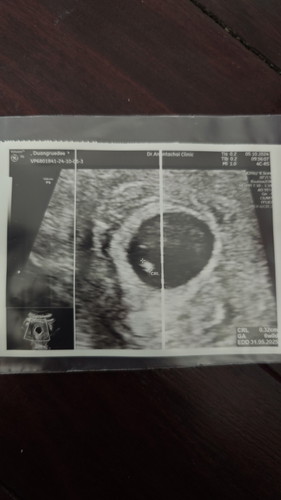

6วีค เจอน้องแล้ว

รอบแรกไปหาหมอซักประวัติหมอบอกประมาณ5วีค ซาวด์ไม่เจออะไรนัดอีก2วีค วันนี้เจอแล้วค่ะ คุณหมอบอกสรุปครรภ์6วีคค่ะ 🥰